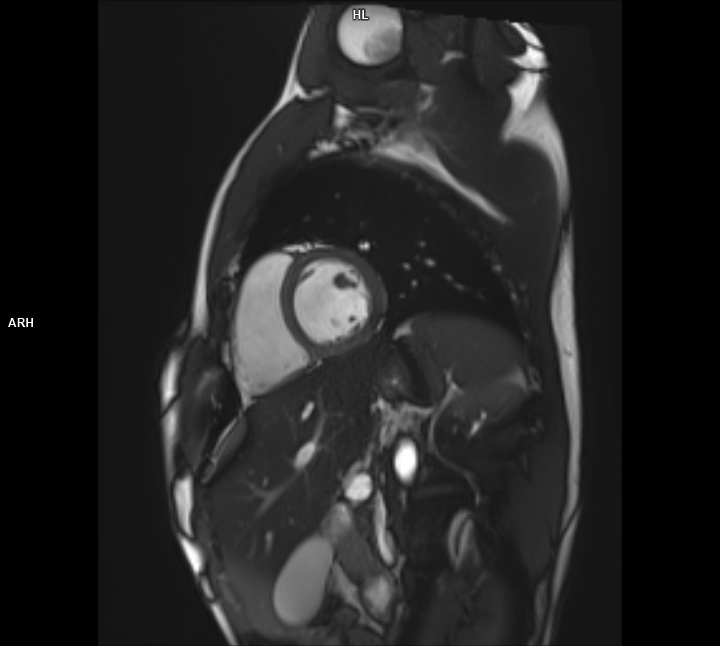

Kardiyolojik Değerlendirme: Kalp dokuları ve damar yapılarının incelenmesinde üstün hassasiyet sağlar.